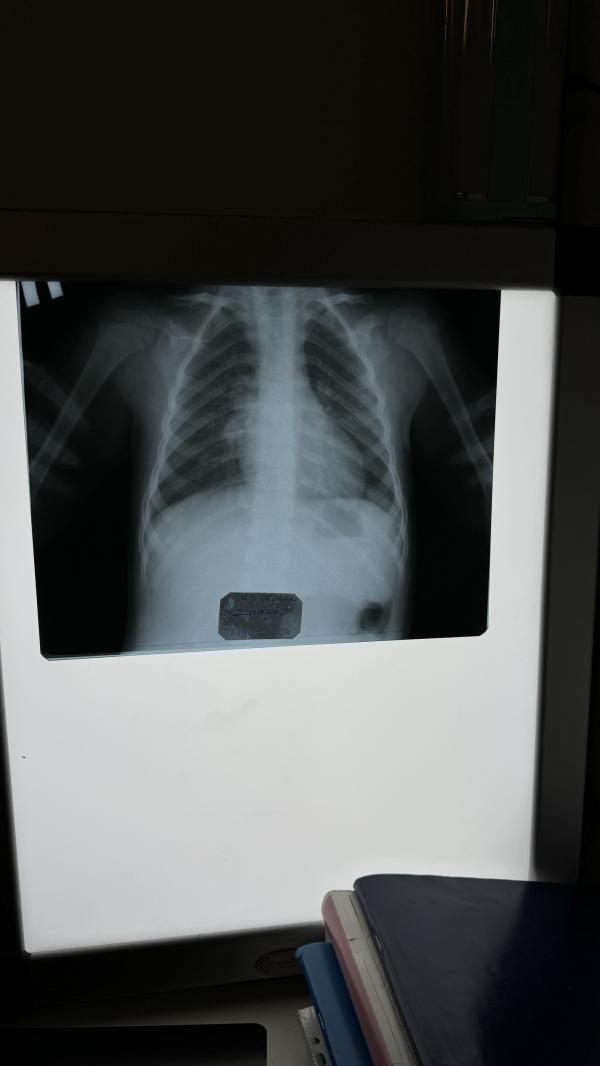

Пневмония у сына правой стороны.

3 года сыну.